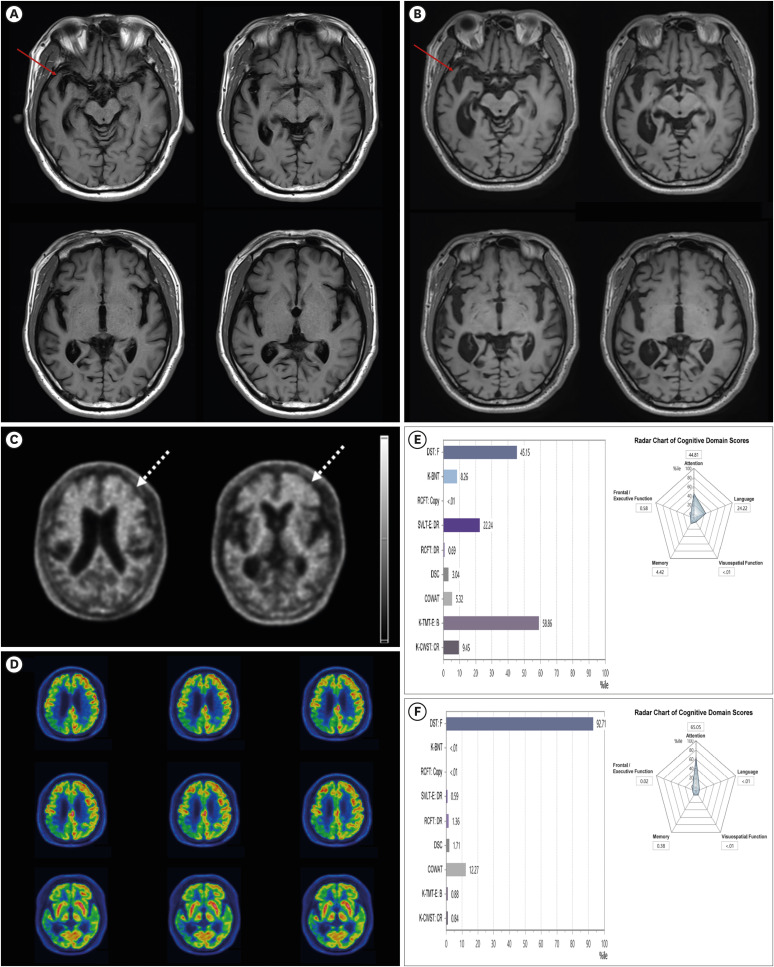

A Case of Combined Corticobasal Degeneration and Alzheimer's Disease Pathology: Clinical Presentation, and Diagnosis.

Dementia and neurocognitive disorders Pub Date : 2025-01-01 Epub Date: 2024-10-14 DOI:10.12779/dnd.2025.24.1.69